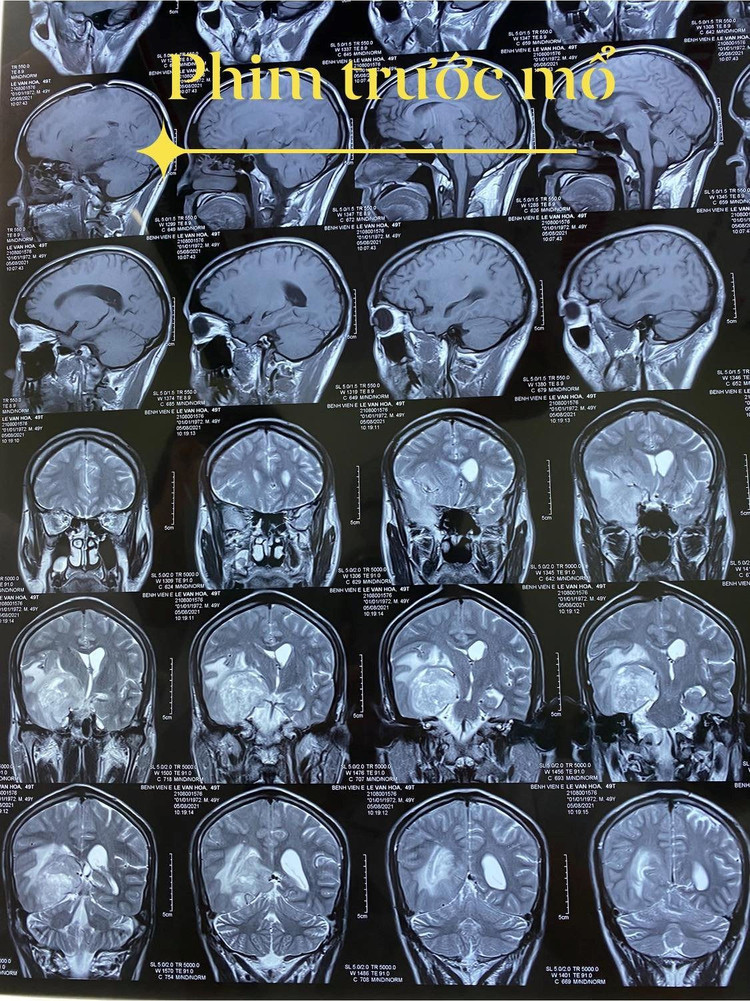

Khối  u của bệnh nhân trên phim trước mổ.

Kết quả thăm khám phát hiện có khối u trong não rất lớn ở thái dương phải, gây phù não nhiều, chèn ép rất nhiều vào thân não, xâm lấn vào lều tiểu não.

TS.BS Nguyễn Đức Anh, Phụ trách khoa Phẫu thuật thần kinh, Bệnh viện E T.Ư – người trực tiếp phẫu thuật cho bệnh nhân cho biết, khối u của bệnh nhân có thể đã có từ trước, phát triển rất lớn gây đau đớn. Nếu không phẫu thuật kịp thời, khối u chèn ép không chỉ ảnh hưởng đến các chức năng sống mà còn đe dọa tính mạng. Chỉ định phẫu thuật được đặt ra, nhưng ca mổ vô cùng khó khăn, phức tạp  vì khối u rất to, giàu mạch nuôi, nằm ở sâu trong não, sát các cấu trúc quan trọng như thân não, bao trong… rất gần các mạch lớn, nguy cơ chảy máu khó cầm, nguy cơ yếu liệt và biến chứng sau mổ rất cao. Hơn nữa, não phù nhiều, ranh giới giữa tổ chức u và não lành rất khó phân biệt.